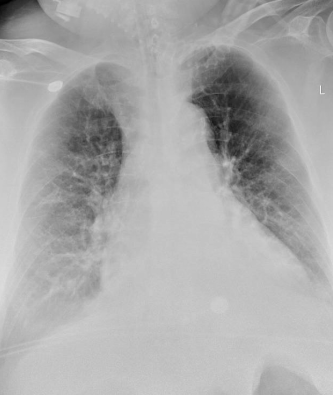

患者由ICU过渡至病房后仍然继续进行呼吸康复训练,增强了主动参与程度,由无创通气过渡至鼻导管氧疗,在病房能够与家人视频,家人的鼓励也增加患者的配合程度,增强康复训练的信心。复查胸部X线片可见患者双肺透亮度较前明显改善(图16)

图片

图16  第三阶段治疗后患者胸部X线片